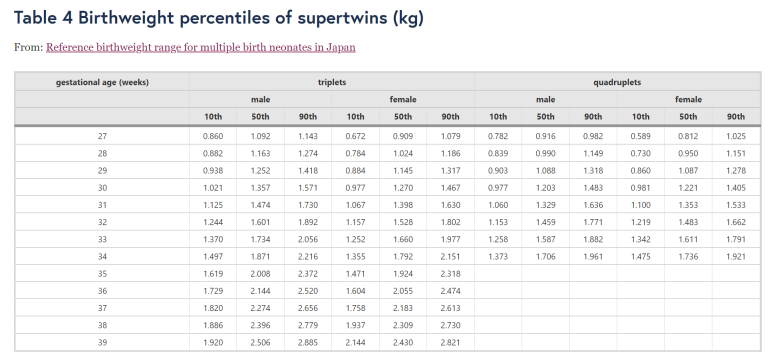

아래 논문에서는 1894명의 세쌍둥이와 206명의 네쌍둥이 출생아를 대상으로 표준편차 낸 것이다.

27주 이전 주수는 없어서 좀 아쉽다 ㅜㅜ 그래도 네쌍둥이도 있다니! 참고해 볼만하다.

출처: https://bmcpregnancychildbirth.biomedcentral.com/articles/10.1186/1471-2393-4-2

https://bmcpregnancychildbirth.biomedcentral.com/articles/10.1186/1471-2393-4-2/tables/4

Reference birthweight range for multiple birth neonates in Japan

Background A reference range for the birthweight of multiple births neonates is necessary for the assessment for intrauterine growth. Methods Pairs of multiple births were identified by birthplace, the ages of the parents, gestational age, and the year and

bmcpregnancychildbirth.biomedcentral.com